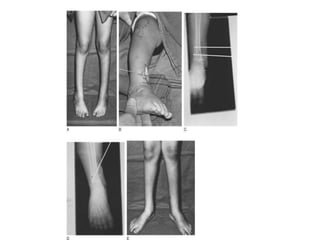

Supramalleolar Osteotomy

• If the toe-in gait persists for 2 years after

clubfoot surgery.

• Reserved only for rotational correction.